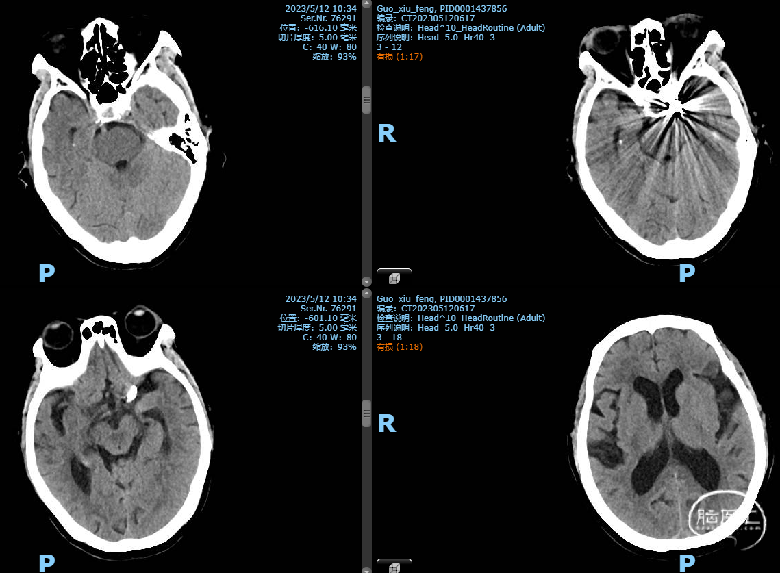

2023-05-12 术后CT

因“突发头痛、呕吐6天”于2023-05-8 12:45 急诊平车入院。神经系统:神志清,精神差,言语流利,双侧额纹对称,双侧瞳孔等大等圆,直径约2.5mm,对光反射灵敏,双侧鼻唇沟对称,口角无歪斜,伸舌居中,颈软无抵抗,四肢肢体肌力检查不配合,肌张力正常,生理反射存在,病理反射未引出。

当地医院头部CT:SAH

初步诊断:1、颅内动脉瘤 2、蛛网膜下腔出血

诊疗计划

急诊造影检查,备颅内动脉瘤栓塞术

2023-05-8 手术

外院首次CT影像片未带,我院复查头部CT,右侧积血较多,故优先处理右侧动脉瘤,尝试裸栓;但左侧颈眼动脉瘤形态不规则,也有可能是责任动脉瘤,拟过几日再支架辅助栓塞。

2023-05-8 手术

手术材料

通路:6F指引管 ENVOY DA导管

微导管微导丝:Echelon10微导管,Synchro-14微导丝

弹簧圈:ORBIT 3.5mm*7.5cm、ev3 2mm*3cm、ev3 1.5mm*2cm

封堵系统:压迫器

2023-05-10 术后CT